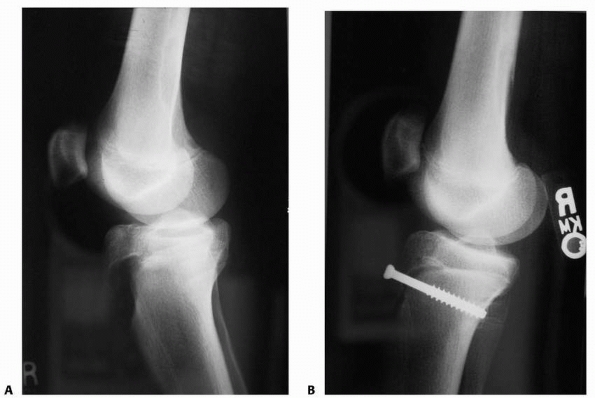

FIGURE 23-4 A.

In a Salter-Harris type II fracture, the side where the fracture occurred through the physis fails in tension, with disruption of the periosteum. The side of the fracture with the Thurstan-Holland fragment failed in compression, with the periosteum usually intact. The intact periosteum can be used for fracture reduction. B. With fracture reduction, the periosteum may become interposed within the fracture site, preventing an anatomic reduction |